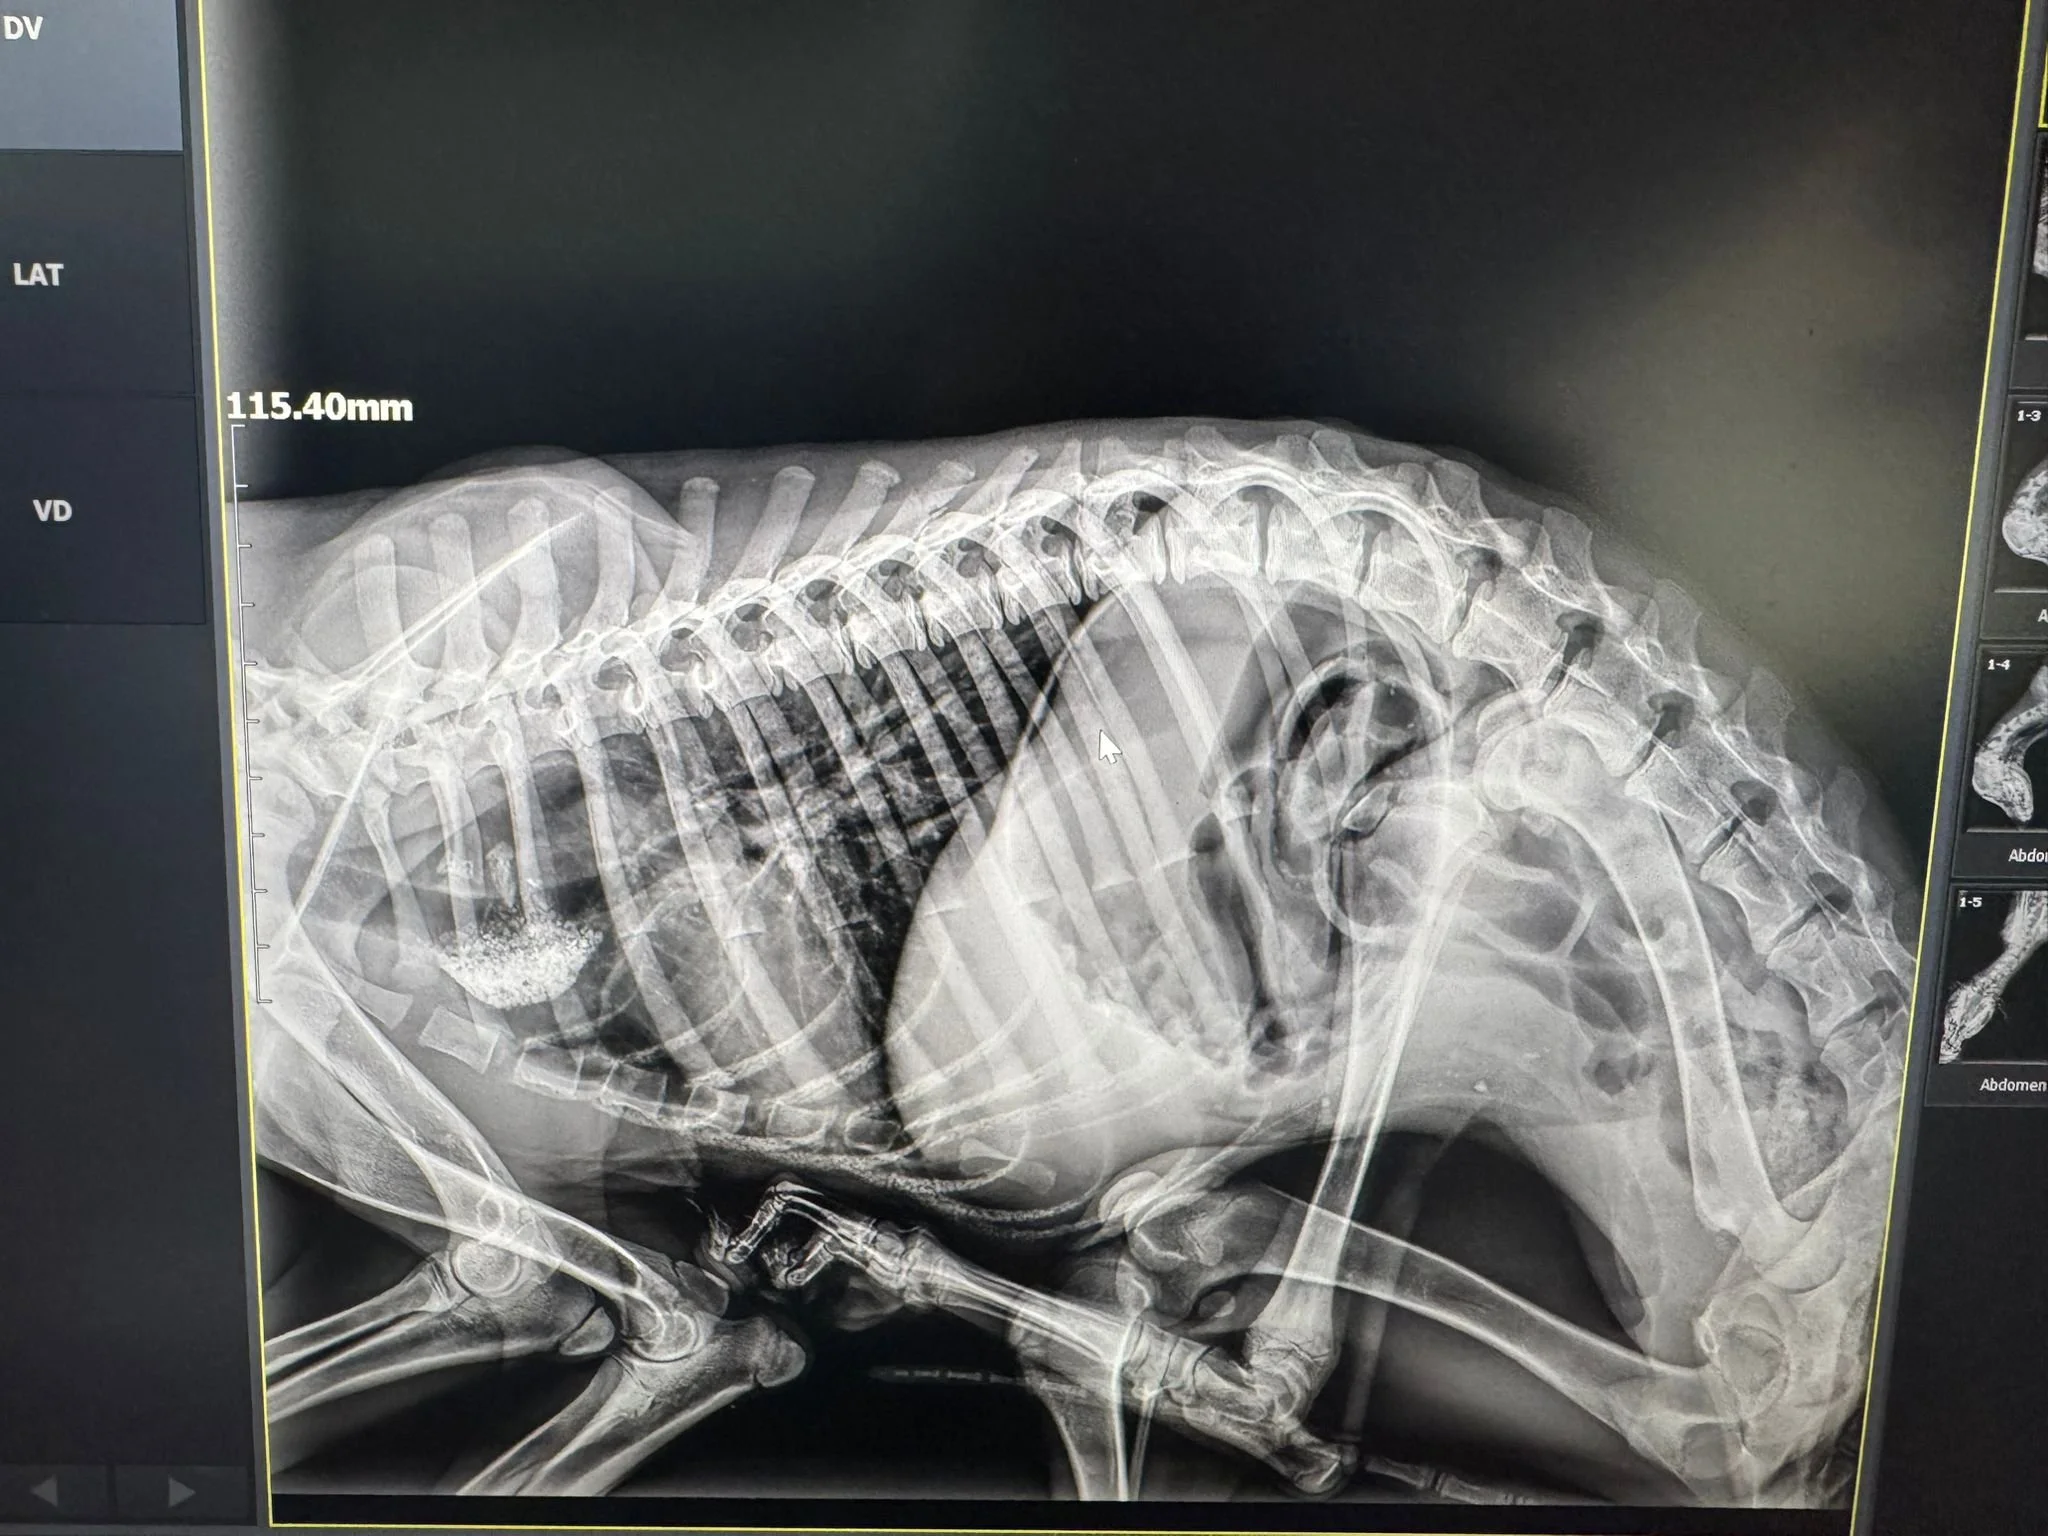

Investigațiile imagistice și corelarea cu tabloul clinic au evidențiat o problemă congenitală rară: o anomalie de arc aortic care genera compresie esofagiană.

În cazul lui Wolfie, o bridă de țesut conjunctiv sau o structură vasculară persistentă comprima esofagul, împiedicând trecerea normală a alimentelor către stomac.

Consecințele erau severe:

• alimentele rămâneau blocate în esofag

• apărea regurgitare constantă

• aportul nutrițional era minim

• dezvoltarea organismului era compromisă

Cel mai probabil, Wolfie trăise toată viața cu senzația permanentă de foame.